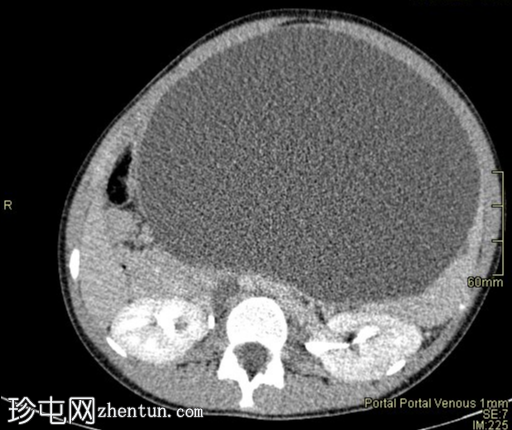

冠状位增强扫描(门静脉期)

脾脏内可见巨大、边界清晰的囊肿,囊肿内有多个较小的囊肿。脾脏被拉伸并覆盖于囊肿之上,形成“爪状征”。囊肿大小为26 cm x 20 cm x 16 cm。囊肿内有单分隔,下壁可见多处钙化。

无实性成分。无子囊肿。囊肿将胃向上推移,将肝脏向右推移,并将肠道推向盆腔。腹主动脉旁可见亚厘米级淋巴结。其他实质性器官均正常。无腹水。骨骼结构正常。

为进一步明确腹部肿块的性质,医生安排了腹部CT检查¹。结果显示,脾脏起源处有一个边界清晰的巨大囊肿,囊肿内包含多个较小的囊肿。该囊肿大小为26 cm x 20 cm x 16 cm。

囊肿下部可见单隔膜和多发钙化灶。无实性成分。无子囊肿。囊肿将胃向上推移,将肝脏向右推移,并将肠道推向盆腔。主动脉旁可见亚厘米级淋巴结。其他所有实质性器官均正常。无腹水。骨骼结构正常。